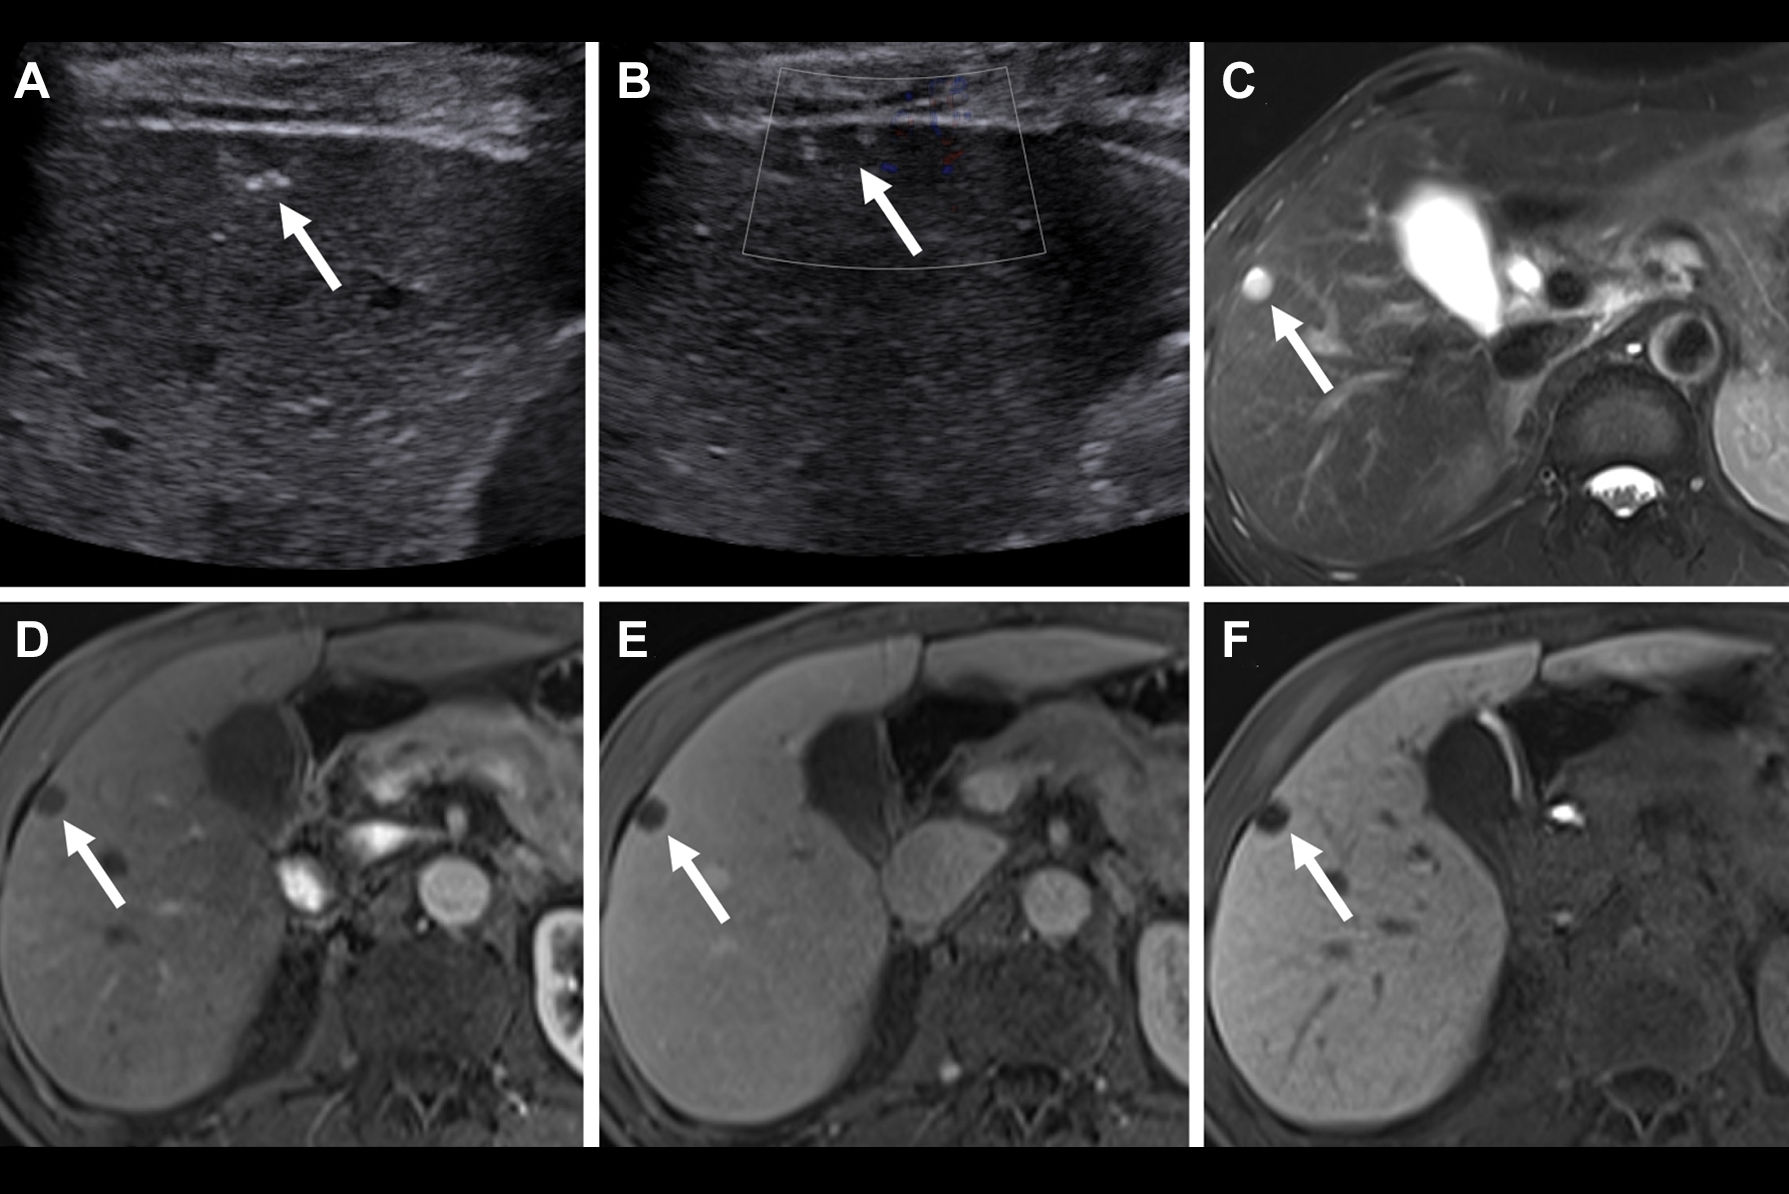

"As a large number of hepatic and renal lesions are detected during initial ultrasound, the ability to perform CEUS at time of initial examination or shortly thereafter can obviate the need for further workup with contrast-enhanced CT or MRI," Streb and colleagues wrote.

Overall, 66.7% of the CEUS exams were considered sufficiently diagnostic to eliminate the need for further workup with CT or MRI. By specific lesion type, 71.2% of CEUS liver exams and 55.2% of CEUS kidney exams were deemed adequately diagnostic to avoid follow-up CT or MRI.